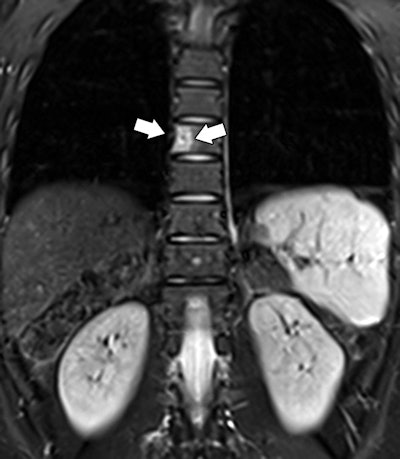

Based on the results, whole-body MRI had a sensitivity of 100%, specificity of 94%, positive predictive value of 25%, and negative predictive value of 100%. Coronal and axial short-tau inversion recovery (STIR) sequences were the most effective for detecting abnormalities.